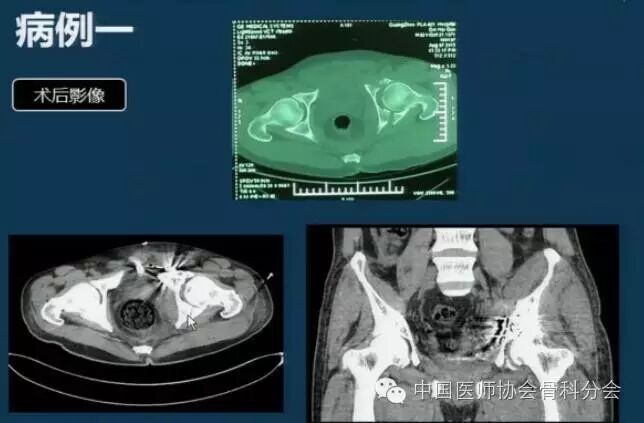

精彩病例展示